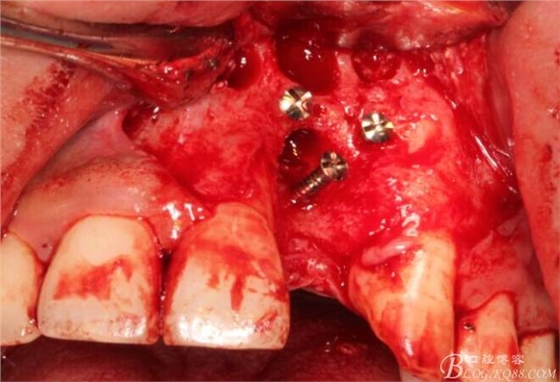

根方用取骨鉆取自體骨。

旋入一長兩短3顆鈦釘。

將自體骨與BIO-OOS骨粉混合植到術(shù)區(qū),蓋生物膜。